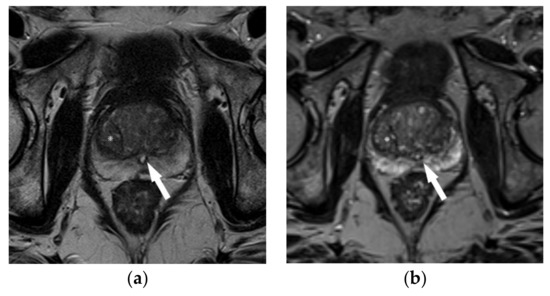

3.1. Use of Dynamic Contrast-Enhanced Sequences